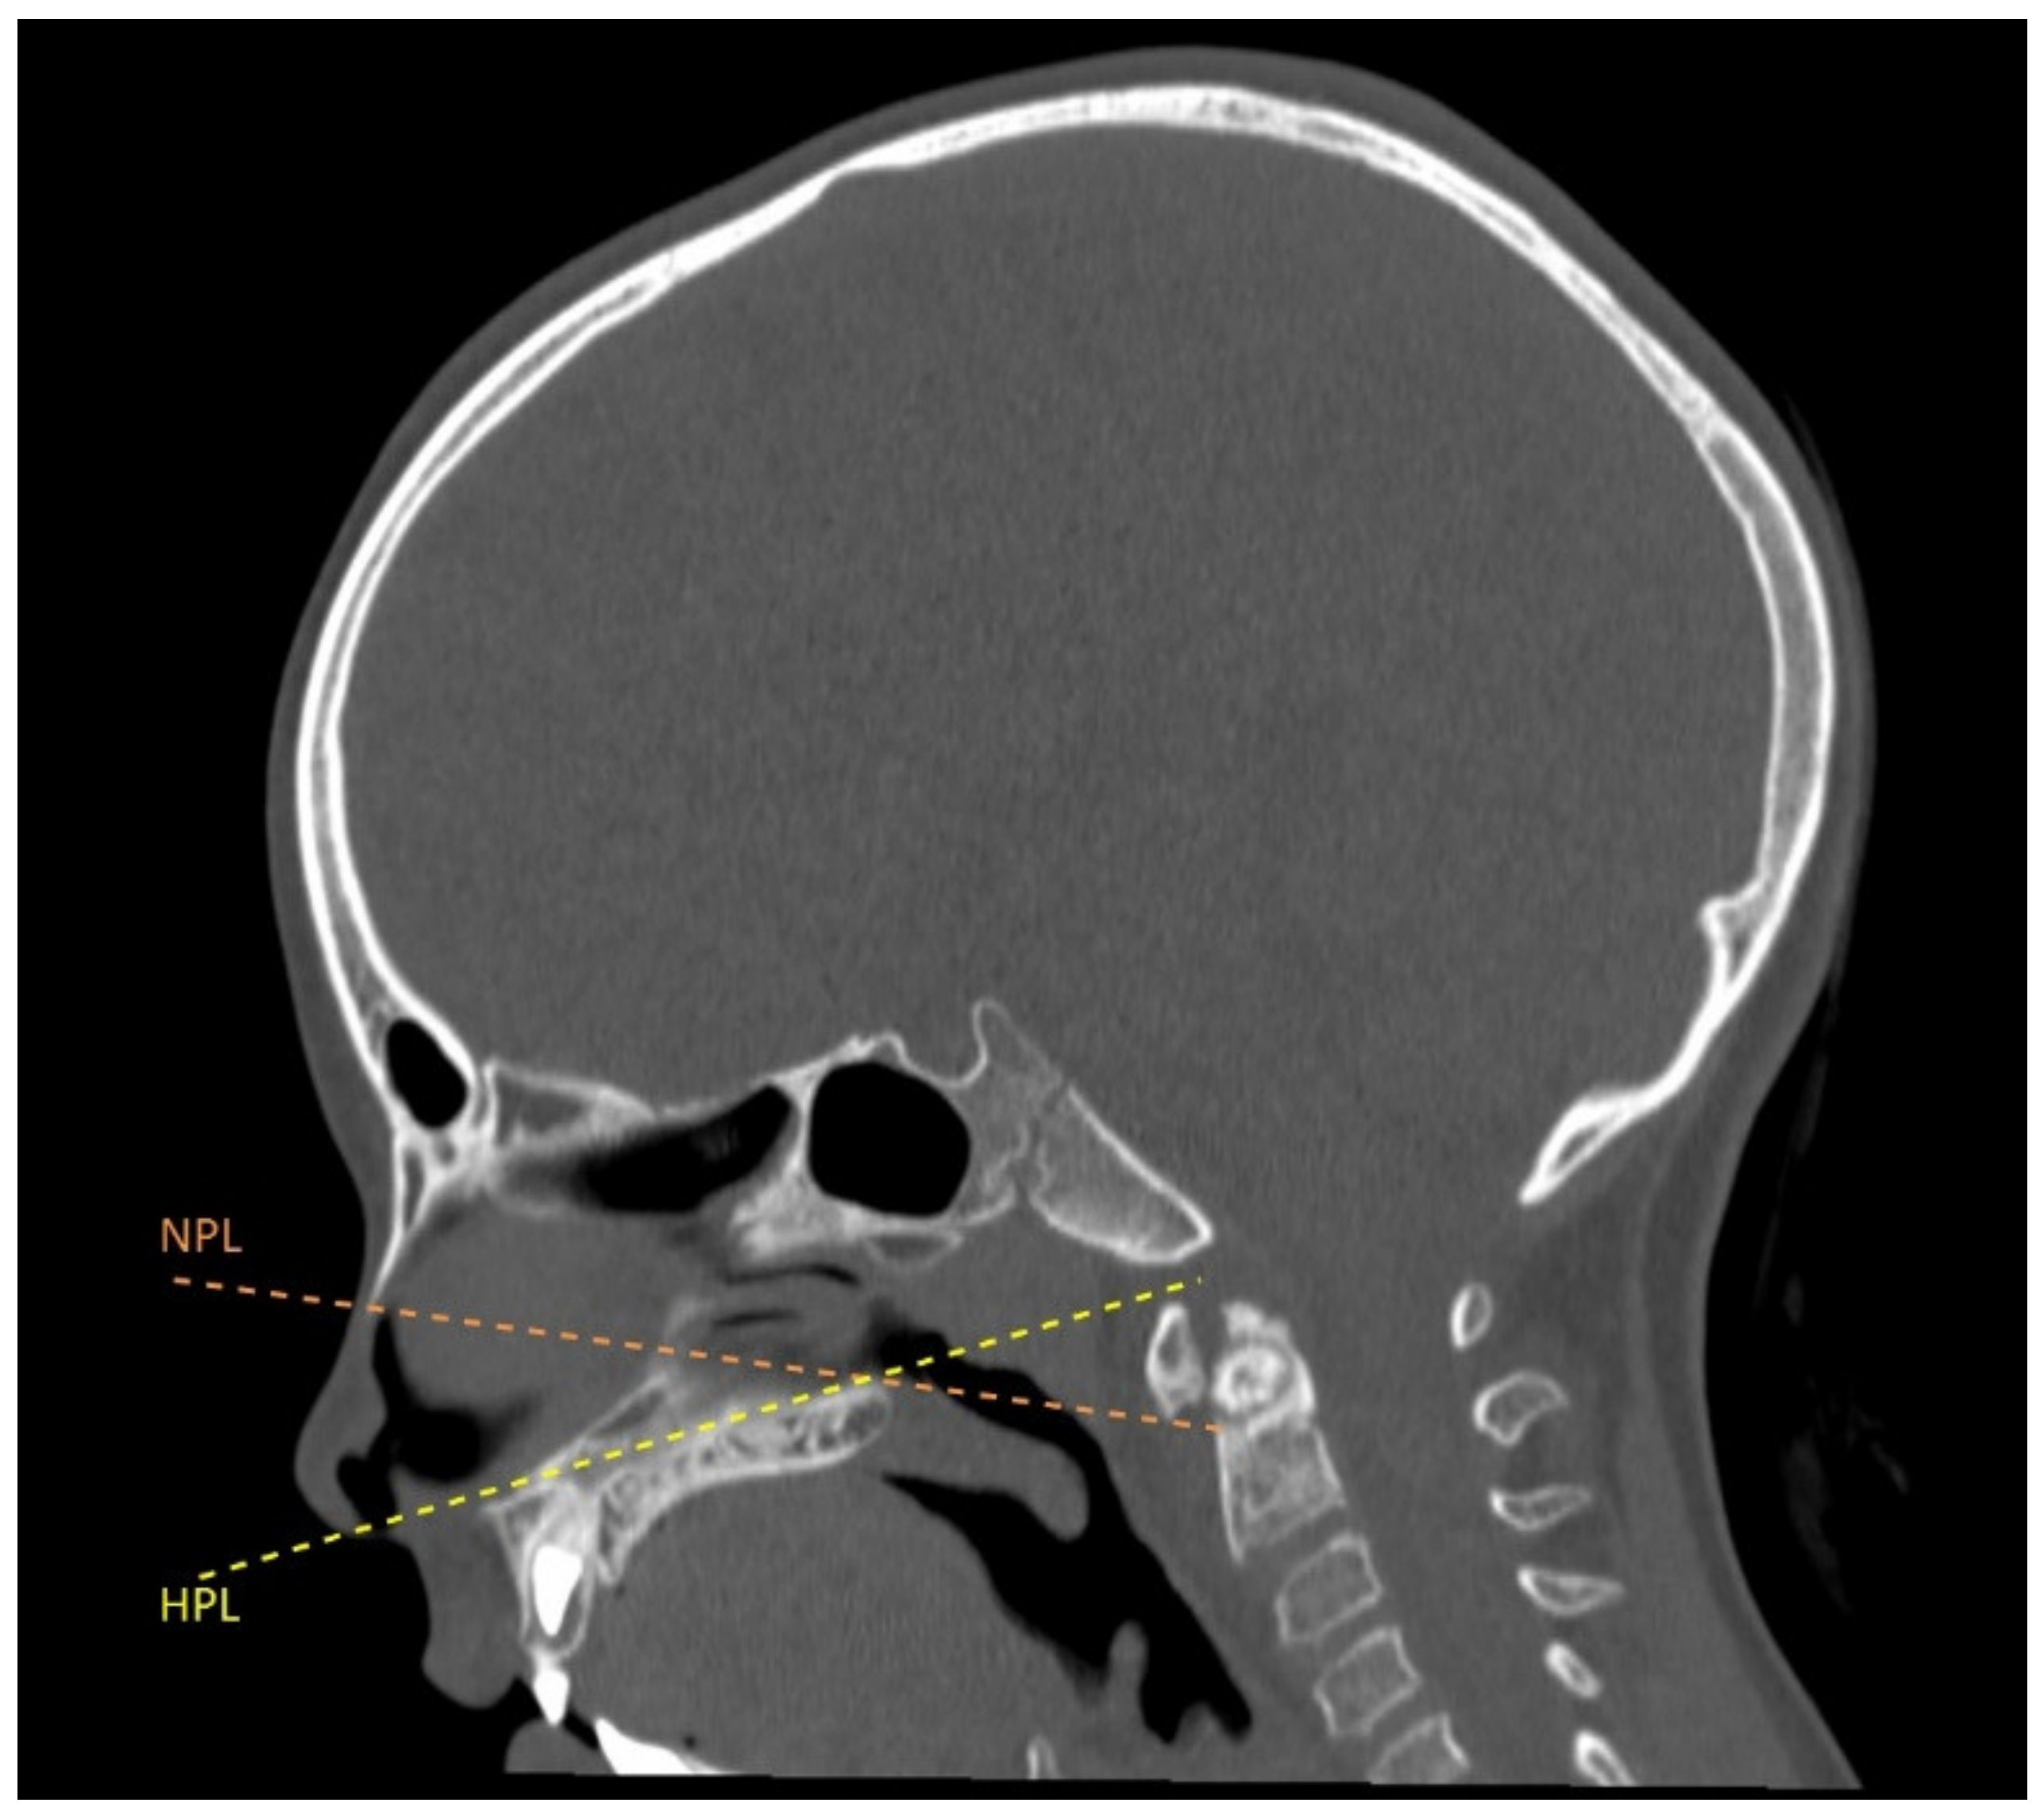

2.1. Technical Note

2.1.2. Surgical Procedure